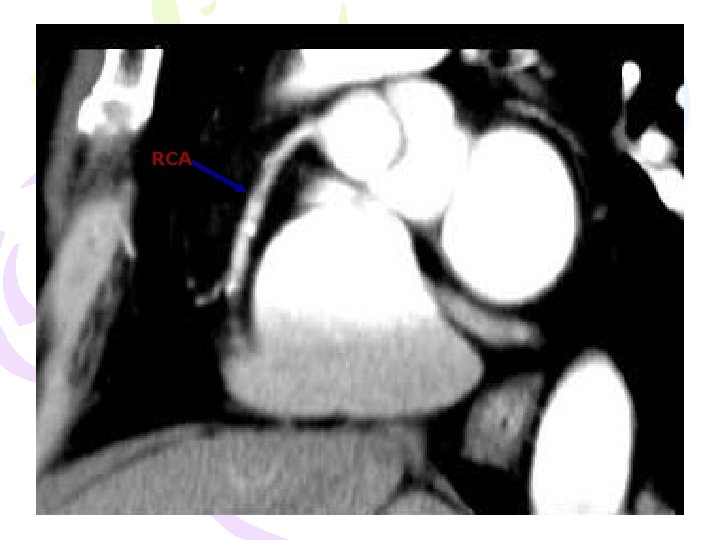

RCA